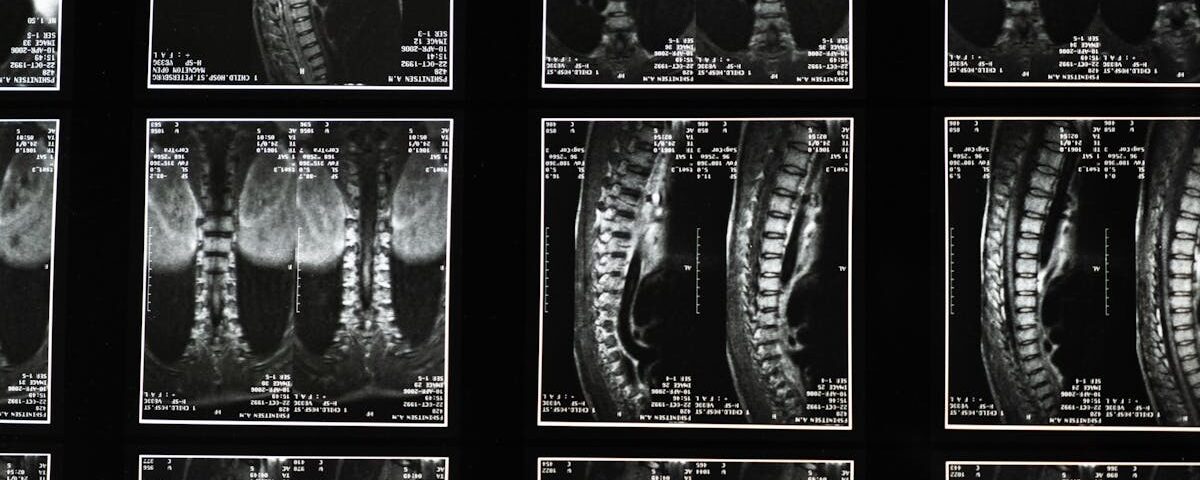

Quels examens permettent de diagnostiquer la sciatique?

Une IRM ou une radiographie est généralement nécessaire pour confirmer la cause de la sciatique.